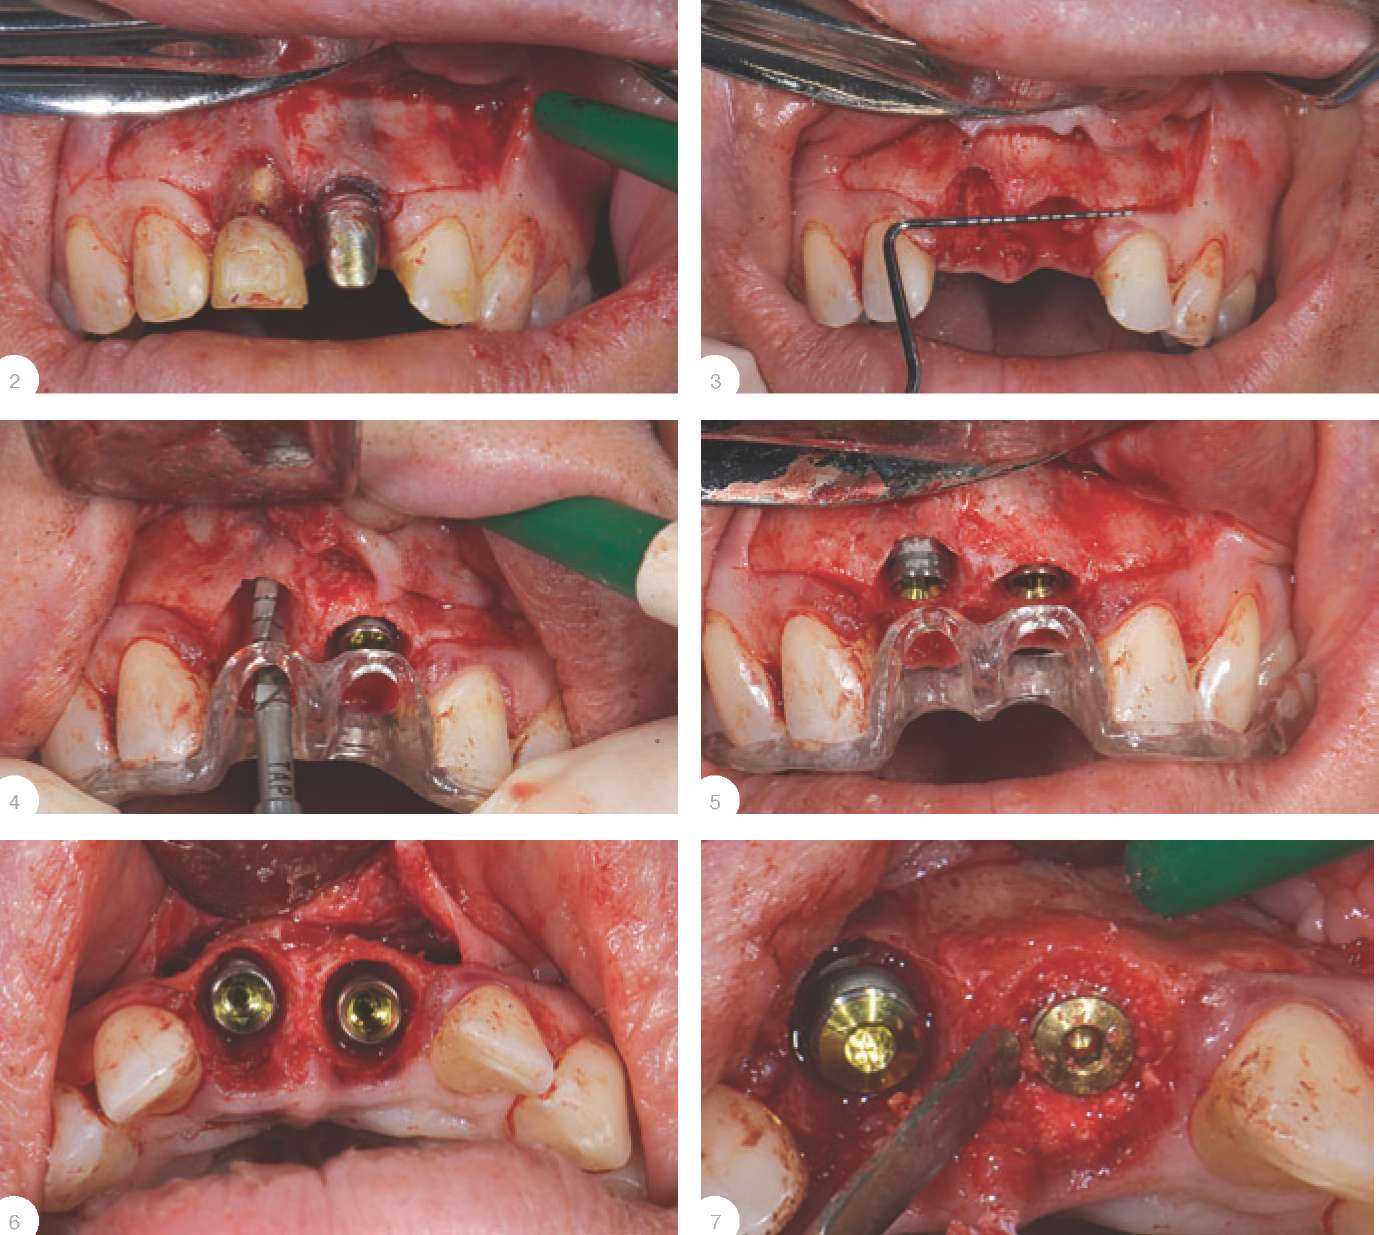

Устанавливая имплантат, необходимо помнить, что крайне нерекомендованным является использование диаметров имплантатов более чем 4,5 мм! Ошибочно суждение некоторых российских хирургов о том, что если размер лунки позволяет устанавливать имплантаты до или более 5 мм, то этооправдано идеальной первичной стабилизацией имплантата. Однако в обозримом будущем касание имплантата к вестибулярной стенке альвеолы даже в верхнейтрети лунки приведет к резорбциистенки, что в свою очередь явится причиной неудовлетворительного эстетического результата. Первичная стабилизация имплантата является, наверно, главным фактором, влияющим на позитивный исход всего лечения, однакодостигать его путем бикортикального заклинивания имплантата влунке удаленного зуба недопустимо. Все, что необходимо сделать -это углубить лунку не менее, чемна 3-4 мм, и сместить ось имплан-тата небно для отсутствия контактас передней стенкой альвеолы повсе протяженности (рис. 2). Расстояние между имплантатом ипередней стенкой должно составлять от 1,5 до 2 мм. Если даннаядистанция превышает указанное значение, то мы рекомендуем использовать аутогенную кость, смешанную в равной пропорции с материалом Bio-Oss, так как последний будет выполнять роль каркасадля поддержки аутокости.Откинут лоскут, планируется удаление 11 и 21 с одномоментной имплантацией (рис. 3).Зубы 11 и 21 удалены (рис. 4). Установлены имплантаты Биого-ризонт диаметром 3,8 (рис. 5).Правильно изготовленный шаблон позволяет позиционировать нетолько ось, но и расположение шейки имплантата (рис. 6).Смещенное в небном направлении положение имплантатов хорошовидно на рис. 7. Аутогенная кость с ветви нижнейчелюсти смешана с Bio-Oss и плотно скондесирована между имплантатом и альвеолой (рис. 8-10). Временное протезирование при немедленной имплантации Временное протезирование с использованием несъемной конструкции, например коронок с винтовой фиксацией для достижения эстетического результата и социальной реабилитации пациента,возможно только при хорошей фиксации имплантата. Если естьмалейшие сомнения по этому поводу, а также при проведении НТР,мы рекомендуем ушивать имплантат и фиксировать конструкцию мериленд. |